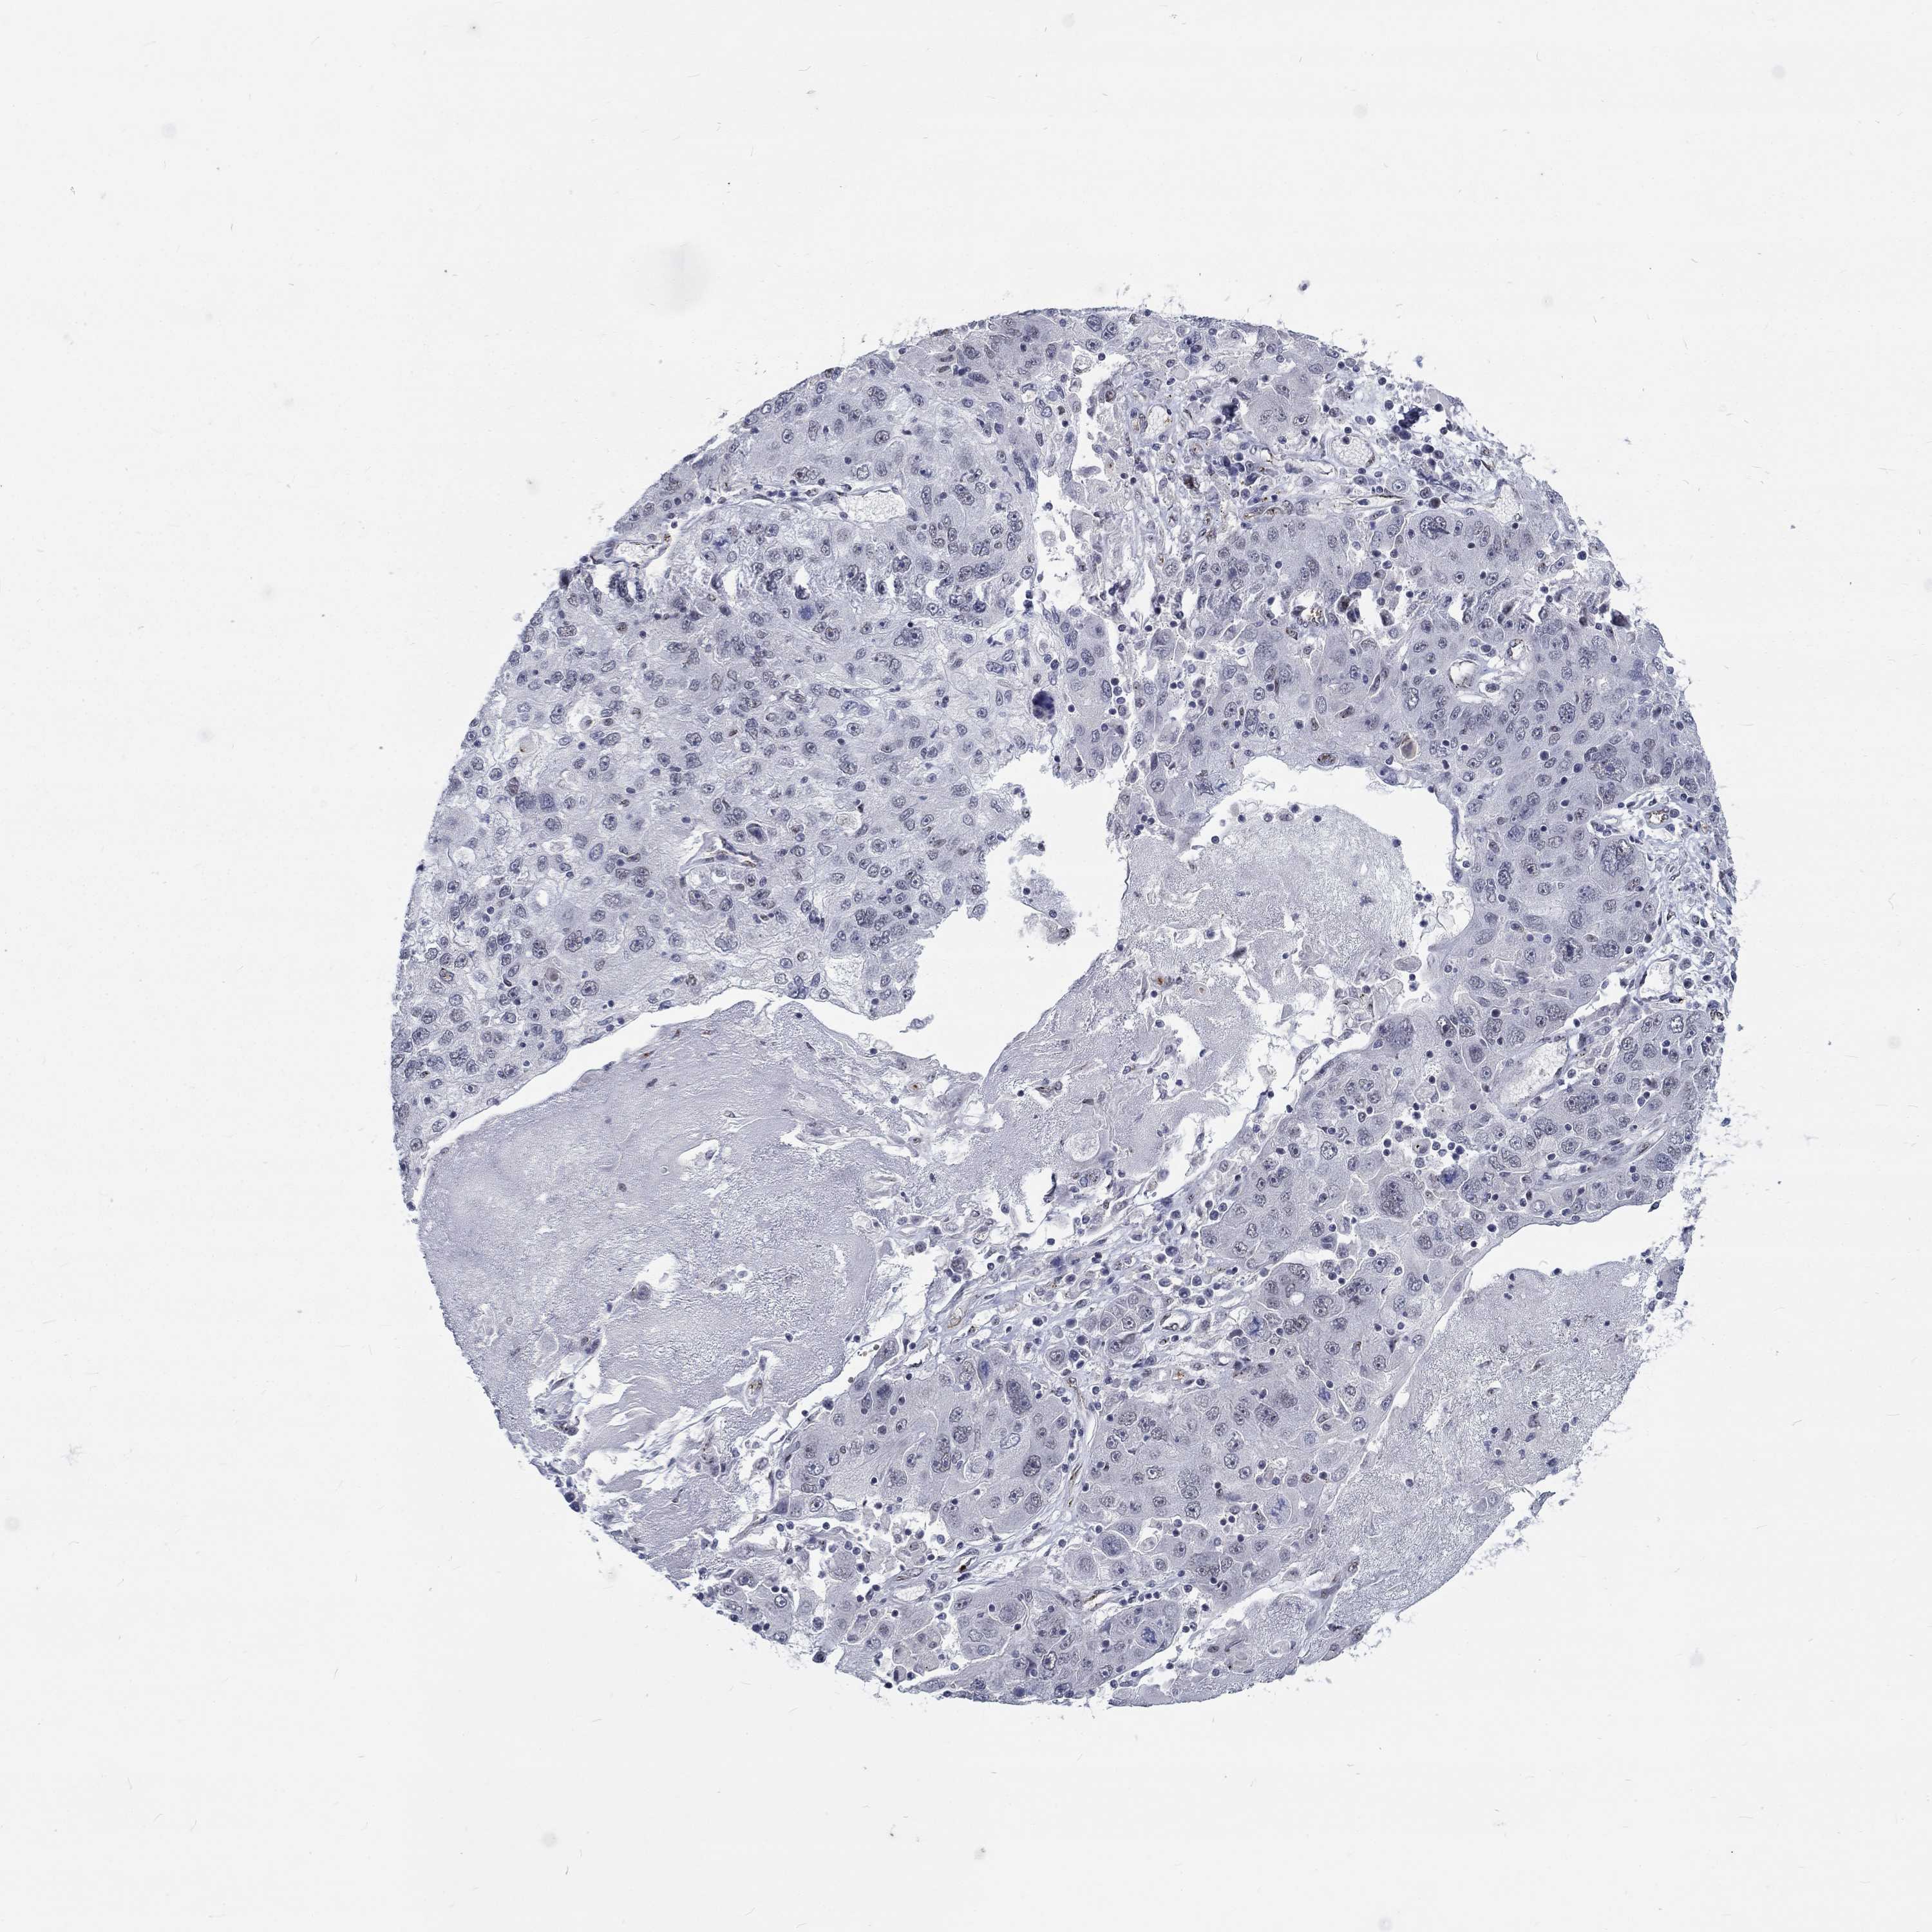

STOMACH CANCER - Protein expressioni

A mouse-over function shows sample information and annotation data. Click on an image to view it in a full screen mode. Samples can be filtered based on level of antibody staining by selecting one or several of the following categories: high, medium, low and not detected. The assay and annotation is described here.

Antibody stainingi

Antibody staining in the annotated cell types in the current human tissue is reported as not detected, low, medium, or high, based on conventional immunohistochemistry profiling in selected tissues. This score is based on the combination of the staining intensity and fraction of stained cells.

Each image is clickable and will lead to virtual microscopy that enables deeper exploration of all samples and also displays staining intensity scores, fraction scores and subcellular localization as well as patient and tissue information for each sample.

Antibody HPA077591

Staining

High

Medium

Low

Not detected

Intensity

Strong

Moderate

Weak

Negative

Quantity

>75%

75%-25%

<25%

None

Location

Nuclear

Cytoplasmic/membranous

Cytoplasmic/membranous,nuclear

Adenocarcinoma, NOS

Adenocarcinoma, High grade